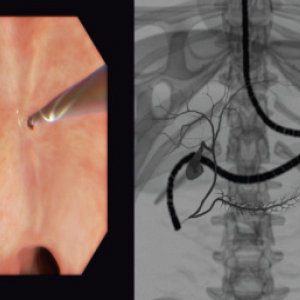

Real-feel surgical simulation. Diagnostic and surgical skills in Endoscopy

EndoVision sets the standard in simulation for hands-on-training in endoscopic procedures. Allowing trainees realistic and safe clinical experiences

EndoVision offers exposure to an extensive library of modules and patient cases to challenge diagnostic and psychomotor skills in preparation for real presentations.

High-precision no-lag instrument tracking system provides accurate, smooth response for all your actions.